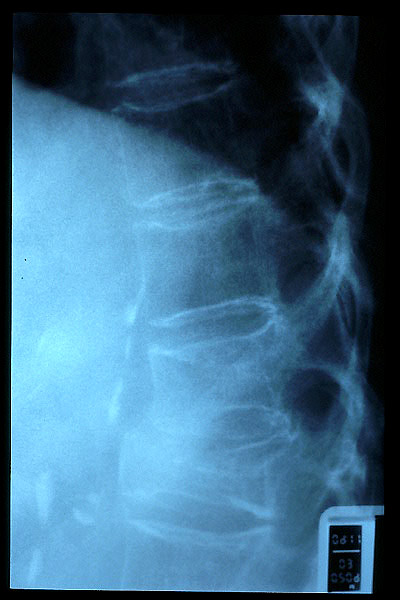

Osteoporosis. Cifosis.

Escoliosis. Espondilolistesis.

Artrosis lumbar con pinzamiento.

Artrosis lumbar

Escoliosis, artrosis, aplastamiento...

Fractura vertebral, aplastamiento

Acuñamiento vertebral traumático

Aplastamiento vertebral. Gas. Osteoporosis.

Aplastamiento vertebral. Osteoporosis.